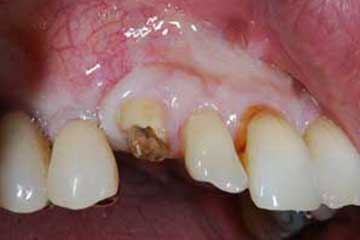

I denti irrecuperabili dell'arcata superiore ed inferiore del paziente di anni 65

sono stati sostituiti da 10 impianti, cioè protesi radicolari endo-ossee che sostengono le protesi fisse superiore ed inferiore.